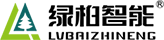

關(guān)于腰椎間盤突出  腰椎間盤突出癥是纖維環(huán)破裂后髓核突出壓迫神經(jīng)根造成以腰腿痛為主要表現(xiàn)的疾病。腰椎間盤退行性改變或外傷所致纖維環(huán)破裂,髓核從破裂處脫出,壓迫腰椎神經(jīng),從而出現(xiàn)腰腿放射性疼痛。  病因: 一、退行性變: 目前認(rèn)為,其基本病因是腰椎間盤的退行性變。退行性變是一切生物生、長、衰、亡的客觀規(guī)律,由于腰椎所承擔(dān)的特殊的生理功能,腰椎間盤的退行性變比 其他組織器官要早,而且進(jìn)展相對要快。這個過程是一個長期,復(fù)雜的過程。所謂腰椎間盤退行性改變:即由于椎間盤受體重的壓迫,加上腰部又經(jīng)常進(jìn)行彎曲、后伸等活動,易造成椎間盤的擠壓和磨損,尤其是下腰部的椎間盤,從而產(chǎn)生退行性改變。腰椎間盤退行性改變是本病發(fā)生的基礎(chǔ)。 二、其他因素: 1、外力作用:在日常生活和工作中,部分人往往存在長期腰部用力不當(dāng)、過度用力姿勢或體位的不正確等情況。例如長期從事彎腰工作的煤礦工人和建筑工人需經(jīng)常彎腰提舉重物。這些長期反復(fù)的外力造成的損傷日積月累地作用于椎間盤,加重了退變的程度。 2、椎間盤自身解剖因素的弱點: (1) 椎間盤在成人之后逐漸缺乏血液循環(huán),修復(fù)能力也較差,特別是在退變產(chǎn)生后,修復(fù)能力更加微弱。 (2) 椎間盤后外側(cè)的纖維環(huán)較為薄弱,而后縱韌帶在腰5、骶1平面時寬度顯著減少,對纖維環(huán)的加強(qiáng)作用明顯減弱。 (3) 腰骶段先天異常:腰骶段畸形可使發(fā)病率增高,這些異常造成椎間隙寬度不等,并常造成關(guān)節(jié)突出,關(guān)節(jié)受到更多的旋轉(zhuǎn)勞損,使纖維環(huán)受到的壓力不一,加速退變。 3、種族、遺傳因素:有色人種發(fā)病率較低,例如印第安人和非洲黑人等發(fā)病率較其他民族明顯要低。  2 病理 腰椎間盤突出癥的病理變化過程大致可分為三個階段: 1、突出前期:髓核因退變和損傷可變成碎塊狀物,或呈瘢痕樣結(jié)締組織,變性的纖維環(huán)可因反復(fù)損傷而變薄變軟或產(chǎn)生裂隙。此期病人可有腰部不適或疼痛,但無放射性下肢痛。也有的人原無病變,可因一次大的暴力引起髓核突出。 2、突出期:外傷或正常的活動使椎間盤壓力增加時,髓核從纖維環(huán)薄弱處或破裂處突出。突出物刺激或壓迫神經(jīng)根即發(fā)生放射性下肢痛,或壓迫馬尾神經(jīng)發(fā)生大小便功能障礙。在老 年患者,可因椎間盤退變,整個纖維環(huán)變得軟弱松弛,椎間盤可呈彌漫性向周圍膨出。 3、突出晚期:腰椎間盤突出后,病程較長者,椎間盤本身和其他鄰近結(jié)構(gòu)均可發(fā)生各種繼發(fā)性病理改變。 3 誘發(fā)因素 腰椎間盤突出癥的基本因素是椎間盤退變,但某些誘發(fā)因素可致使椎間隙壓力增高,引起髓核突出。此種誘發(fā)因素常與以下因素有關(guān): 1. 年齡因素:腰椎間盤突出癥的好發(fā)年齡在30-50歲,平均手術(shù)年齡在40歲,因此退變可能是其重要因素。 2. 身高與性別:有人認(rèn)為身材過高也會易發(fā)腰突癥,而男性發(fā)病率是女性的5倍。 3. 增加腹壓:臨床上有約1/3的病人在發(fā)病前有明確的增加腹壓的因素,如劇烈的咳嗽、噴嚏、屏氣、用力排便等。使腹壓增高,破壞了椎節(jié)與椎管之間的平衡狀態(tài)。 4. 不良體位:人在完成各種工作時,需要不斷更換各種體位以緩解腰部壓力,如長期處于某一體位不變,即可導(dǎo)致局部的累積性損傷。特別是長期處于不良姿勢更容易誘發(fā)本病。 5. 職業(yè)因素:重體力勞動者發(fā)病率最高,白領(lǐng)勞動者最低。汽車駕駛員由于長期處于顛簸和振動狀態(tài),椎間盤承受的壓力大且反復(fù)變化,也易誘發(fā)椎間盤突出。 6. 受寒受濕:寒冷或潮濕可引起小血管收縮、肌肉痙攣,使椎間盤的壓力增加,可能造成退變的椎間盤破裂。     癥狀: 腰椎間盤突出癥患者最多見的癥狀為疼痛,可表現(xiàn)為腰背痛、坐骨神經(jīng)痛,典型的坐骨神經(jīng)痛表現(xiàn)為由臀部、大腿后側(cè)、小腿外側(cè)至跟部或足背的放射痛。據(jù)臨床統(tǒng)計,約95%的腰突癥患者有不同程度的腰痛,80%的患者有下肢痛。特別是腰痛,不僅是腰椎間盤突出最常見的癥狀,也是最早出現(xiàn)的癥狀之一。    檢查: 1、X線:腰椎間盤所包括的髓核、纖維環(huán)和軟骨板密度均較低,在X線下并不顯影,因此臨床上腰突癥患者的腰椎X線平片可僅有一些非特異性的變化,甚至無異常變化。因此單純腰椎平片并不能作為有無腰椎間盤突出癥的直接依據(jù),但X線能發(fā)現(xiàn)腰椎的退行性改變和結(jié)構(gòu)異常,對提示椎間盤的退變有重要意義,并且能排除其他的一些腰椎疾患,如腰椎結(jié)核、腫瘤和腰椎滑脫等。典型的腰椎間盤突出癥患者通過病史、體征和X線平片即能作出初步的診斷。 2、CT檢查:腰椎的CT可以清楚地顯示椎間盤突出的部位、大小、形態(tài)和神經(jīng)根、硬脊膜受壓的情況,同時還可顯示黃韌帶肥厚、小關(guān)節(jié)增生、椎管和側(cè)隱窩狹窄等情況。對腰椎間盤突出癥診斷的準(zhǔn)確率達(dá)到80%-92%。 3、核磁共振(MRI):核磁共振沒有輻射,可以多方位成像(橫斷面、冠狀面、矢狀面和斜面),對解剖細(xì)節(jié)顯示較好,對組織結(jié)構(gòu)的細(xì)微病理變化更敏感(如骨髓的浸潤),可以排除神經(jīng)和脊柱腫瘤等。對于一些落到椎管的髓核組織也不會遺漏。 4、脊髓造影:脊髓造影利用椎管內(nèi)蛛網(wǎng)膜下腔的空隙,注入造影劑后在X線下攝片,顯示椎管內(nèi)部結(jié)構(gòu)。目前常用水溶性造影劑,能較清晰地顯示硬膜腔、馬尾神經(jīng)和神經(jīng)根鞘,對腰椎間盤突出癥的診斷可達(dá)90%左右,主要X線表現(xiàn)為硬膜囊壓迫征象和神經(jīng)根鞘壓迫征象。但由于CT和MRI在臨床的廣泛應(yīng)用,無創(chuàng)傷且診斷率更高,脊髓造影在臨床上的應(yīng)用已經(jīng)大大減少,而且由于它副作用較大,甚至可能造成截癱等嚴(yán)重情況,目前主張慎重選用。 5、肌電圖:肌電圖是對周圍神經(jīng)與肌肉的電生理檢查方法,可用于觀察并記錄肌肉在靜止、主動收縮和支配其的周圍神經(jīng)受刺激時的電活動,同時也可用來測量周圍神經(jīng)的傳導(dǎo)速度。在腰椎間盤突出癥上,肌電圖主要通過檢查雙下肢肌肉的興奮性來反映相應(yīng)神經(jīng)根的狀態(tài),并根據(jù)異常電活動的分布范圍來判斷椎間盤突出和神經(jīng)根受壓的節(jié)段。在脊神經(jīng)根和馬尾神經(jīng)受壓的病人,肌電圖陽性率可達(dá)80%-90%,但與CT和MRI相比并不是首選的檢查手段,可用于輔助診斷和判斷神經(jīng)根的受壓情況,同時也可以用來作為判斷治療后神經(jīng)根恢復(fù)情況的指標(biāo)之一。    預(yù)防: 腰椎間盤突出癥是在退行性變基礎(chǔ)上積累傷所致,積累傷又會加重椎間盤的退變,因此預(yù)防的重點在于減少積累傷。 日常注意事項: 1.平時要有良好的坐姿,睡眠時的床不宜太軟。 2.長期伏案工作者需要注意桌、椅高度,定期改變姿勢。 3.職業(yè)工作中需要常彎腰動作者,應(yīng)定時伸腰、挺胸活動,并使用寬的腰帶。 4.應(yīng)加強(qiáng)腰背肌訓(xùn)練,增加脊柱的內(nèi)在穩(wěn)定性,長期使用腰圍者,尤其需要注意腰背肌鍛煉,以防止失用性肌肉萎縮帶來不良后果。 5.如需彎腰取物,最好采用屈髖、屈膝下蹲方式,減少對腰椎間盤后方的壓力。    治療: (一)中醫(yī)外敷療法: 腰椎間盤突出可以外貼 腰突正骨膏,其有效成分可透入皮膚產(chǎn)生活血,止痛,化淤,通經(jīng)走絡(luò),開竅透骨,祛風(fēng)散寒等效果,并通過藥物的歸經(jīng)作用而調(diào)理機(jī)體陰陽平衡,滲透于表皮,刺激神經(jīng)末梢,促進(jìn)局部血液微循環(huán),扶正固本、改善體質(zhì),從根本上、全方位針對腰椎疾病病機(jī)特點而發(fā)揮療效,改善病變周圍組織營養(yǎng),起到修復(fù)骨病組織的作用,最終達(dá)到治療目的。 (二)自我治療: 1.腹肌鍛煉: 也就是仰臥起坐。每次做十個,每天三次。(可根據(jù)患者的體質(zhì)來定,不可逞強(qiáng))。 2.交叉扭腰: 兩腳分開與肩寬,腳尖向內(nèi)兩臂伸直,一手在體側(cè),一 手舉過頭頂。如果右手在上,先向左側(cè)后方擺。左側(cè)相反。于此同時腰部也隨之扭動,左右各100次。 3.抱膝觸胸: 處于仰臥位,雙膝屈曲,手抱住膝部,使盡量靠近胸部,然后放下,一上一下為一個動作,可持續(xù)30個。 4.腰背肌鍛煉: 處于平臥,雙膝彎曲放在床上,然后用力將臀部抬起,離開床面10厘米。這時您會感覺到腰背部在用力,堅持5秒鐘,反復(fù)10下。  (三)非手術(shù)治療: 非手術(shù)療法是治療腰椎間盤突出癥的基本療法,約80%以上的患者經(jīng)保守治療均可得到緩解和痊愈。其主要療法有: 1.日常家庭治療:早期腰椎間盤突出癥,癥狀輕微,不需要做特殊的治療。第一,注意臥床休息,避免腰椎受外力壓迫,第二,應(yīng)用其他方法積極鍛煉腰部肌肉力量。 2.牽引治療; 3.推拿按摩治療; 4.物理治療; 5.消炎鎮(zhèn)痛藥物; 6.減輕神經(jīng)根水腫藥物。 (四)推拿治療: 1.解除腰臀部肌肉痙攣 2.拉寬椎間隙,降低盤間壓力 3.增加椎間盤外壓力 4.調(diào)整后關(guān)節(jié),松解粘連 5.促使受損傷的神經(jīng)根恢復(fù)功能 (五)微創(chuàng)治療: 微創(chuàng)治療方法的目的是消除腰椎間盤突出的髓核以解除對神經(jīng)的壓迫。微創(chuàng)治療技術(shù)采用可視設(shè)備,創(chuàng)口不足一厘米有些甚至不足一毫米。消融或摘除髓核,從根本上解除致病因素,因而能夠取得很好的效果。 (六)手術(shù)治療: 腰椎間盤突出癥的手術(shù)原則是嚴(yán)格無菌操作,盡量保留不必去除的骨結(jié)構(gòu)和軟組織結(jié)構(gòu),以最小的創(chuàng)傷達(dá)到足夠的顯露,仔細(xì)徹底地去除病變組織,達(dá)到治療目的。   綠柏相關(guān)產(chǎn)品:  懸吊訓(xùn)練療法是康復(fù)醫(yī)學(xué)中以持久改善肌肉骨骼疾病為目的的,應(yīng)用主動治療和訓(xùn)練的一個總的概念整合,是一種運(yùn)動感覺的綜合訓(xùn)練系統(tǒng),包括診斷與治療兩大系統(tǒng)。 產(chǎn)品特點: 1.電腦軟件管理系統(tǒng),涵蓋患者信息管理、評估、訓(xùn)練、量表、報告、視頻教學(xué)六大模塊,輕松實現(xiàn)評估與訓(xùn)練一體化管理; 2.多點多軸設(shè)計,滿足不同治療方案設(shè)計; 3.懸吊工作站及各個懸吊點,均能實現(xiàn)任意位置移動,一鍵解鎖,省時省力; 4.實時力反饋,精準(zhǔn)量化弱鏈測試及懸吊治療全過程,給治療師及患者最直觀的效果呈現(xiàn); 5.智能神經(jīng)肌肉促通裝置,可根據(jù)評估結(jié)果設(shè)置治療模式、頻率、時間等相關(guān)參數(shù),讓懸吊康復(fù)更加高效有針對性; 6.外觀高端大氣,結(jié)構(gòu)穩(wěn)固,給患者安全保障,增加治療信心。  |